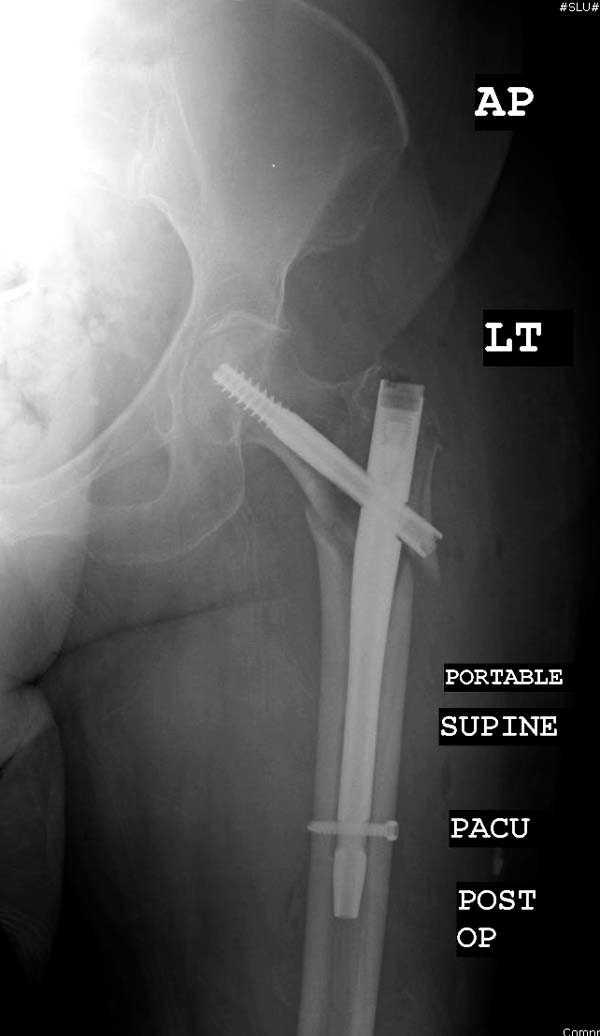

Здесь представлен случай, где в послеоперационном периоде обнаружена техническая ошибка, Gamma 3 установлен с нарушением методики. Больная в 91 лет, прооперирована через день после поступления и выписана через 48 часов.

При первом послеоперационном поликлиническом осмотре больная предъявила жалобы на боли в бедре. В серийных снимках обнаружен продольный перелом верхнего отдела бедра.

Считаем, что техническая ошибка произошла во время установки гвоздя, когда рассверливанию канала не уделили должного внимания. Канал остался узковат, и гвоздь был забит с силой. Полная нагрузка конечности приостановлена на две недели, и боли в конечности изчезли. Больная начала нагрузку и перелом срастается.-- Djoldas Kuldjanov, M.D.Associate ProfessorDepartment of Orthopedic SurgerySt. Louis University

Мне думается, что варусное положение проксимального отломка на последующих снимках не более чем проекционный феномен. Раскол же диафиза вдоль, наверняка, связан с чрезмерно насильственным введением штифта. Вообще, при реверсивных, да и обычных вертельных переломах, многие давно отказались от короткой Гаммы в пользу long-версии. Но в любом случае надо быть на 100 уверенным в подготовке канала.

Перелом А3, подвертельный, вероятно, на длинной версии гвоздя такого бы не произошло

eto nestabil'nui perelom. nado bylo stavit' gamma long. kanal uzkii (bylo vidno). mesiaz ne nagrujat', vse srastetsia!